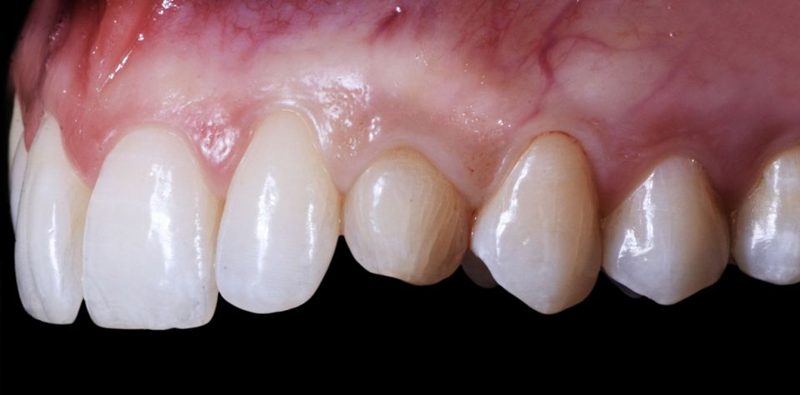

口外检查中,面部评价显示面部对称、比例匀称。微笑分析显示中线矢状面与微笑中线重合,上切牙和尖牙的暴露率为90%(图1)。微笑还显示侧切牙形状不同,与对侧恒尖牙相比,左上乳尖牙更短、更窄、颜色更黄(图2-4)。

Fig. 2: Frontal view of the patient’s smile.

Fig. 3: Right lateral view of the patient’s smile.

Fig. 4: Left lateral view of the patient’s smile.

Fig. 5: Intraoral frontal view

Fig. 6: Intraoral view: The discrepancy between upper canines and lateral incisors is clear. Note that the deciduous tooth is shorter than the contralateral, both at the occlusal and at the gingival side.

Fig. 7: Magnification of the deciduous tooth: A wide amount of keratinized gingiva is shown.